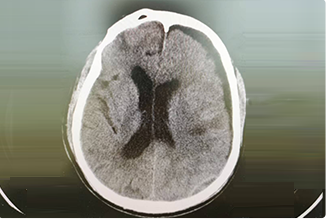

精通顱內(nèi)動脈瘤介入栓塞和手術(shù)夾閉雙技術(shù),系統(tǒng)掌握腦動靜脈畸形、頸內(nèi)動脈海綿竇漏、硬腦膜動靜脈漏等顱內(nèi)血管疾病的診療和手術(shù),精通頸動脈、椎動脈狹窄的血管內(nèi)重建技術(shù),以及頸動脈狹窄的內(nèi)膜剝脫手術(shù)技術(shù)。在顱內(nèi)腫瘤、椎管內(nèi)腫瘤、顱腦損傷、高血壓腦出血等疾病的診治和手術(shù),腦功能性疾病立體定向手術(shù)治療等方面也積累了豐富的經(jīng)驗。

擅長腦血管病(出血與缺血)的神經(jīng)介入與微創(chuàng)手術(shù),能熟練開展腦外傷、重度顱腦損傷的救治工作。